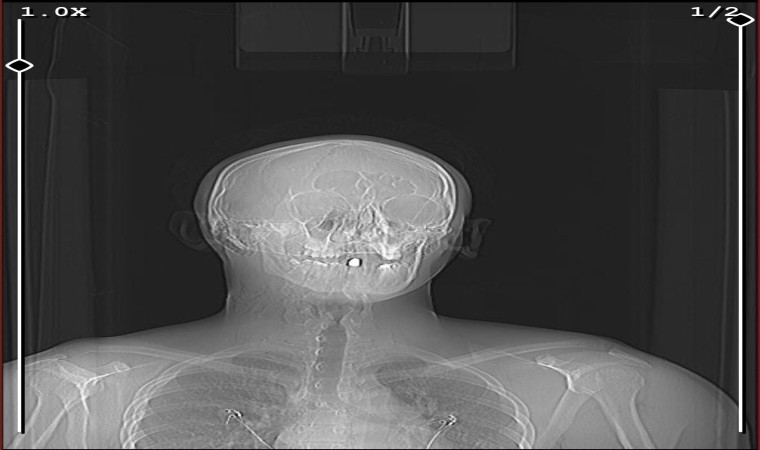

Pendik’te arkadaşlarıyla dondurma almaya giden 17 yaşındaki genç, cadde üzerinde seyir halinde oldukları aracın içerisinden rastgele açılan maganda kurşununun hedefi oldu. Kurşun 17 yaşındaki gencin boynundan girip ağzında kaldı. Ateş açan şahıslar ise olay yerinden kaçarak uzaklaştı.

Olay, geçtiğimiz Pazartesi günü gece 02.00 sıralarında Pendik’te Velibaba Mahallesi’nde meydana geldi. Edinilen bilgiye göre, 17 yaşındaki Aykan Yazar arkadaşıyla birlikte dondurma yemeye gitti. Yazar evine döndüğü sırada, aracıyla seyir halindeyken havaya ateş açarak ilerleyen kimliği belirsiz bir magandanın kurşununun hedefi oldu. Kurşun Yazar’ın ensesinden girerek ağzında kaldı. Şans eseri hayatta kalan Aykan Yazar ihbar üzerine olay yerine gelen ambulans ile ekipleri ile hastaneye kaldırıldı. Polis ekipleri ise kimliği belirsiz magandayı yakalamak için çalışma başlattı.